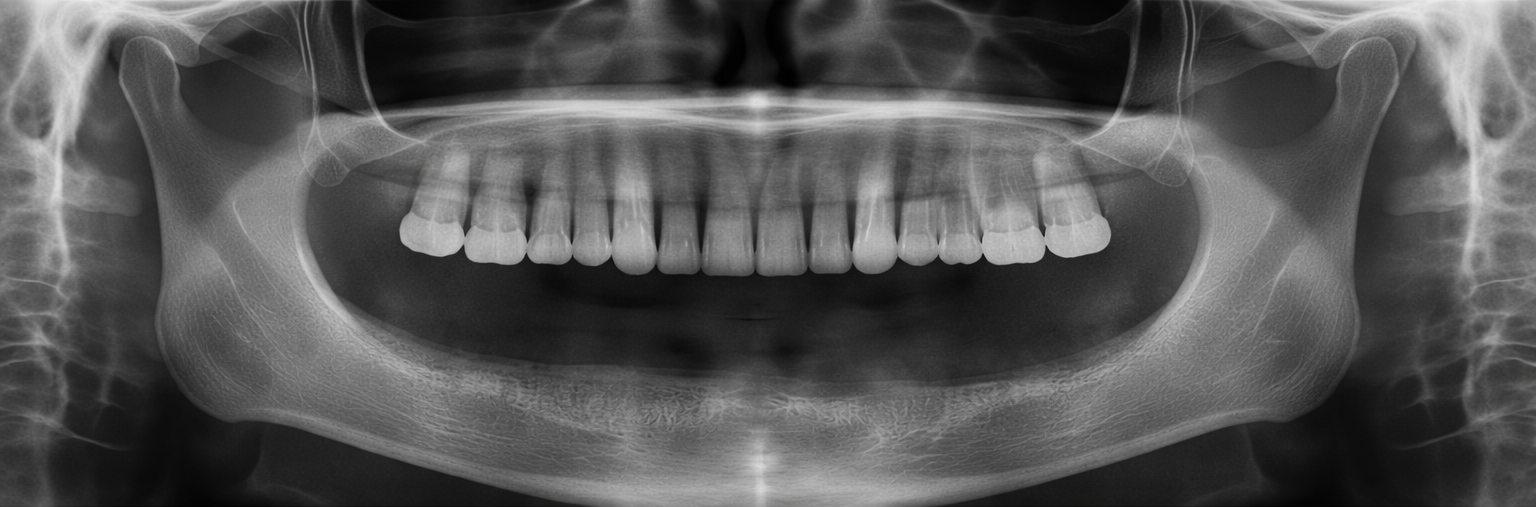

Önce & Sonra

Gerçek hasta sonuçları – sürükleyerek karşılaştırın

Tüm Ağız İmplant

Önce Önce

Sonra Sonra

Sürükleyin

Tek Diş İmplant Tedavisi

İmplant Tedavisi